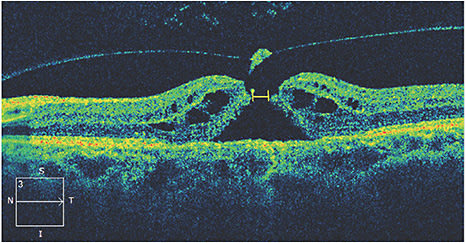

Aside from FTMH size, another preoperative OCT finding that may be associated with the likelihood of a FTMH to close is a slight lifting of the hole edges with the presence of cystoid macular edema (Figure 1).

For reasons not completely understood, patients with these findings tend to have better closure rates. One theory is that these findings indicate a hole of shorter duration.